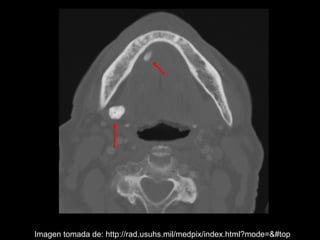

La sialolitiasis es la formación de obstrucciones mineralizadas en las glándulas salivales, causadas por el depósito de calcio y fósforo. Puede presentarse en las glándulas salivales mayores y menores, causando inflamación e hinchazón e incluso dolor durante las comidas. Los sialolitos se ven en radiografías como densidades radiopacas de varias formas y tamaños dentro de los conductos glandulares. El diagnóstico diferencial incluye otras imágenes radiopacas en los tejidos blandos.